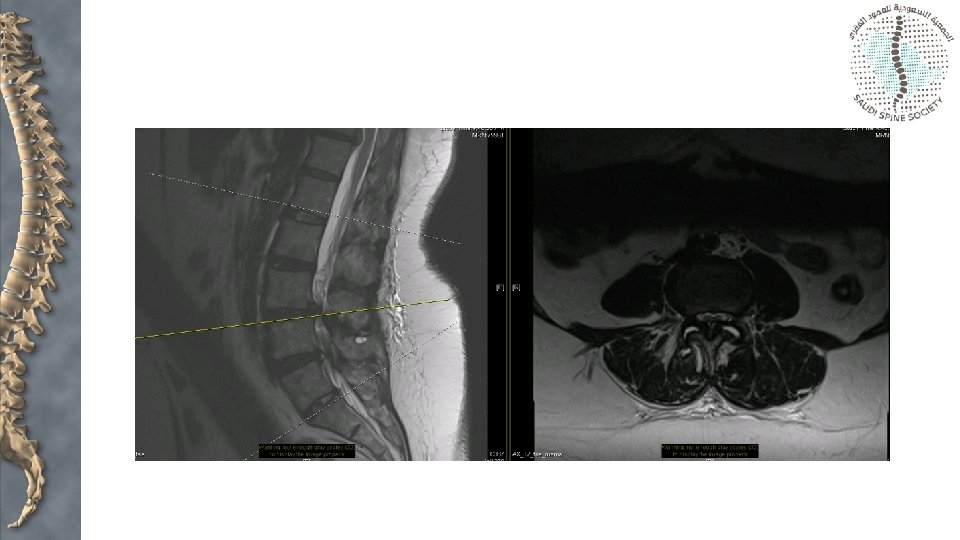

Assessment • X-rays: • • • Anteroposterior Lateral Oblique views CT scan Bone scan MRI

Spinal canal stenosis: facet joint orientation “Sagittal” “Coronal”

Spinal canal stenosis: facet joint orientation • Facet orientation > 45 degrees is 25 times more likely to develop degenerative spondylolisthesis most commonly at L 4/5 • Women: Men = 5: 1 • African-American women > Caucasian women